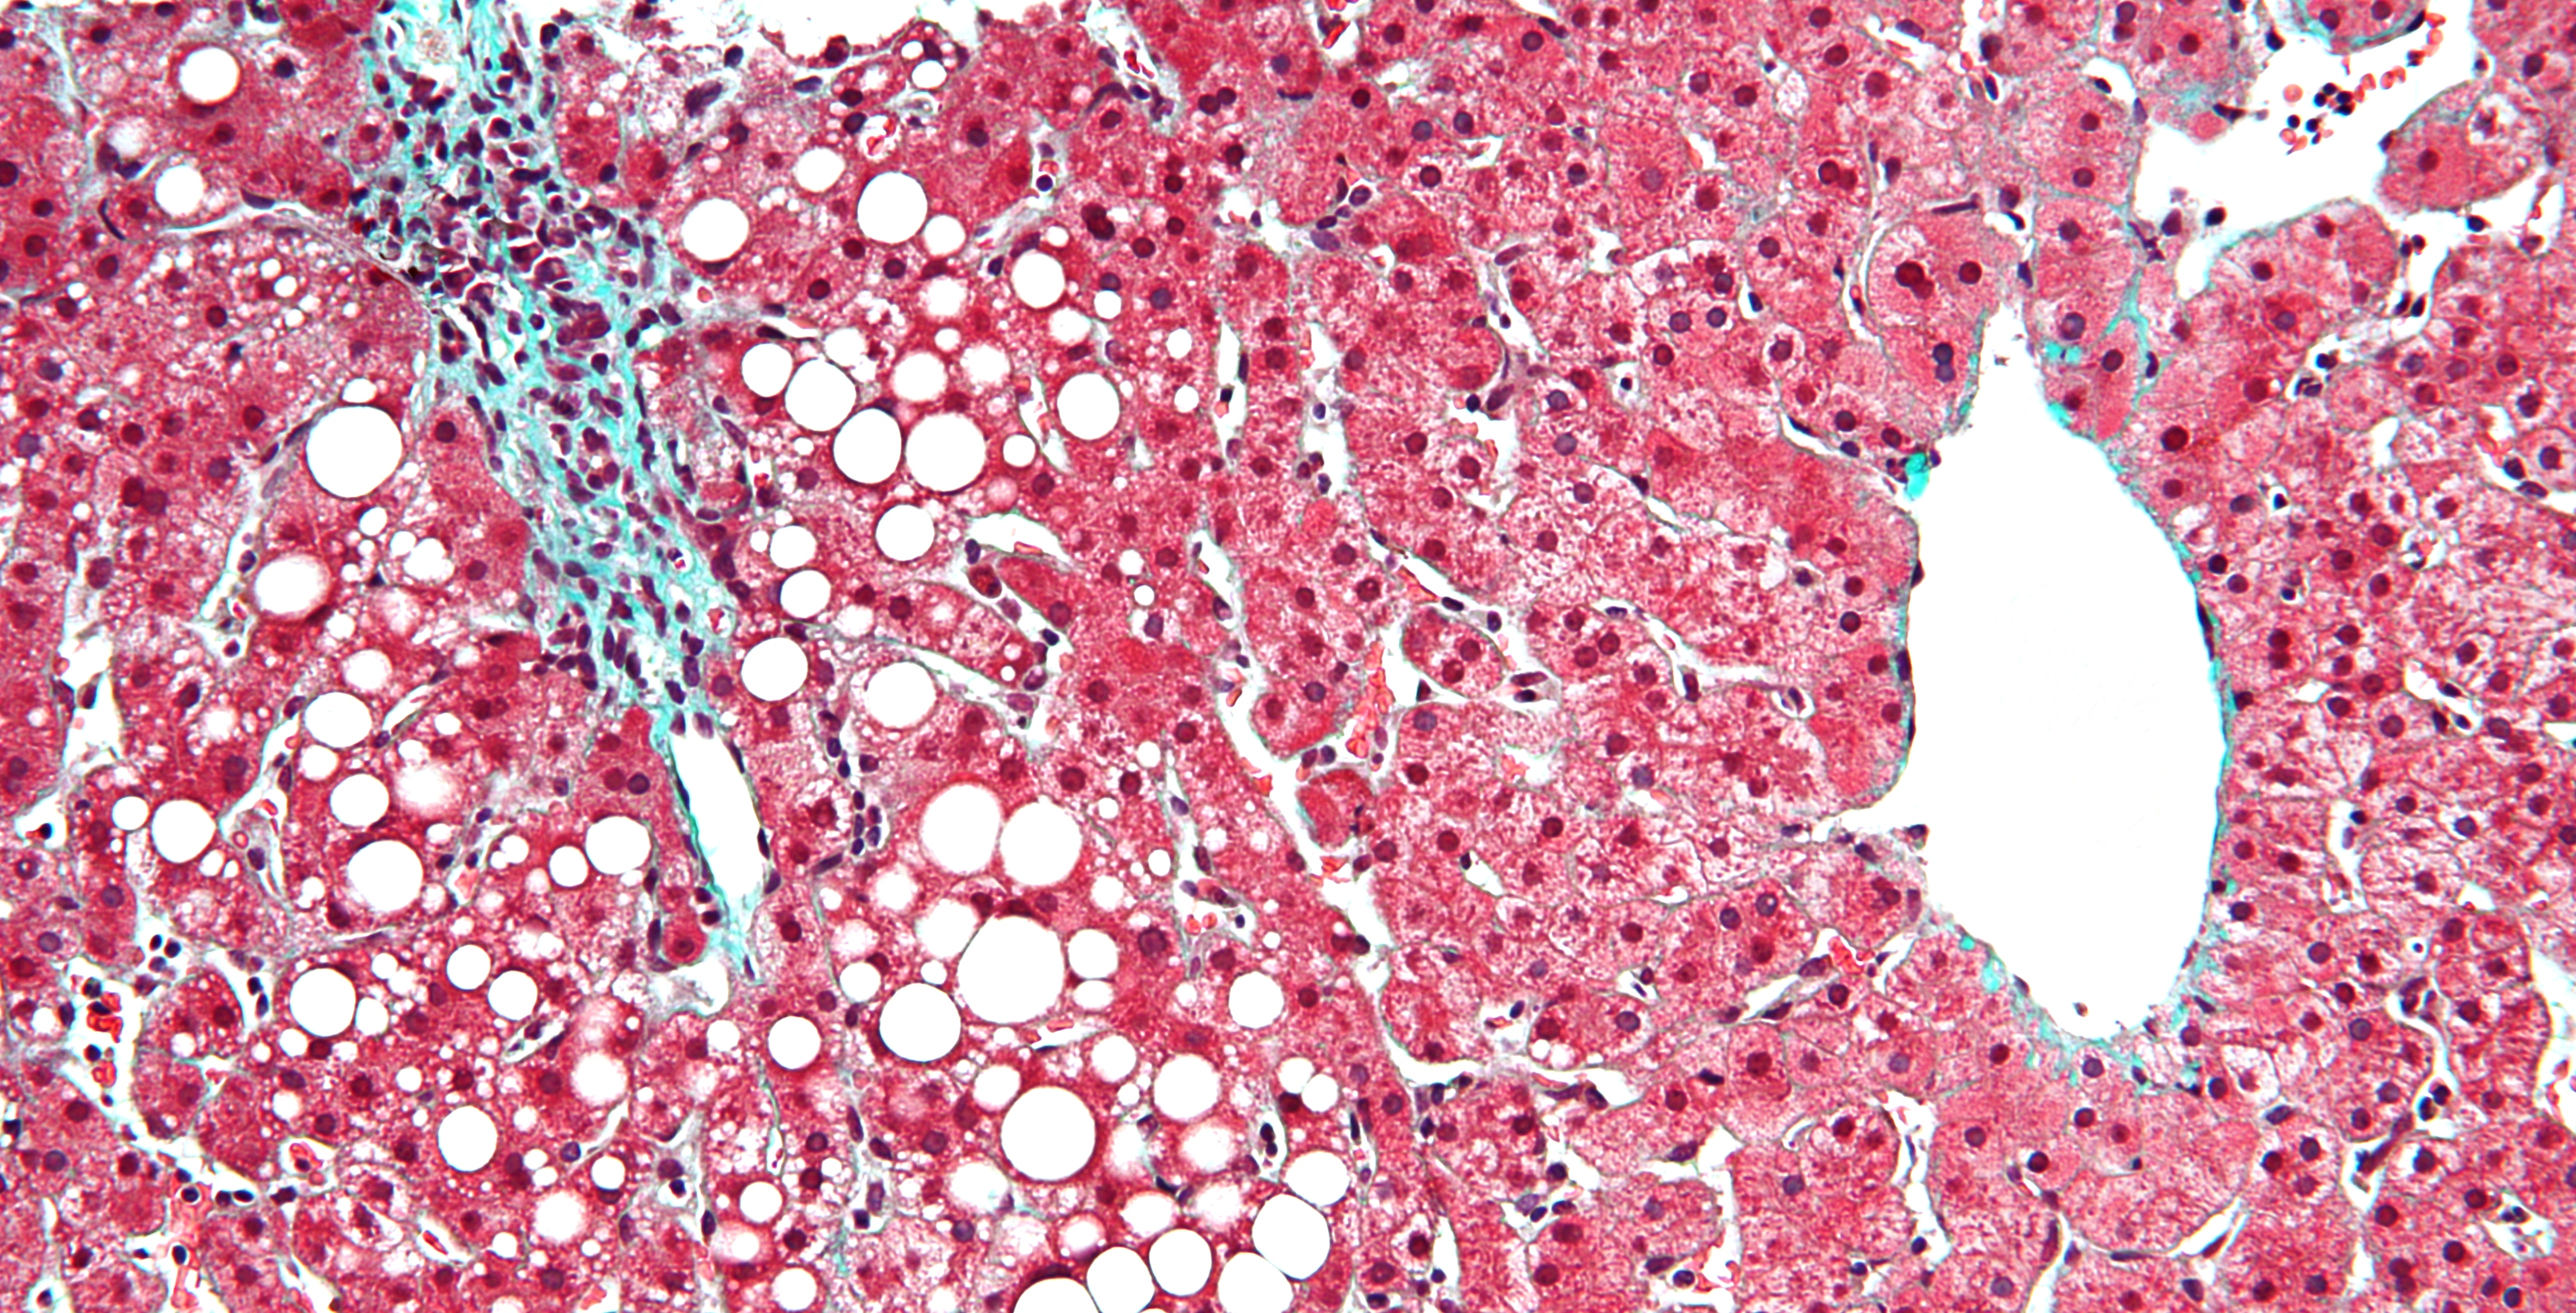

Looking at something that usually goes unnoticed to most people, gives me the ability to express things that would otherwise secretly carry on their daily tasks.